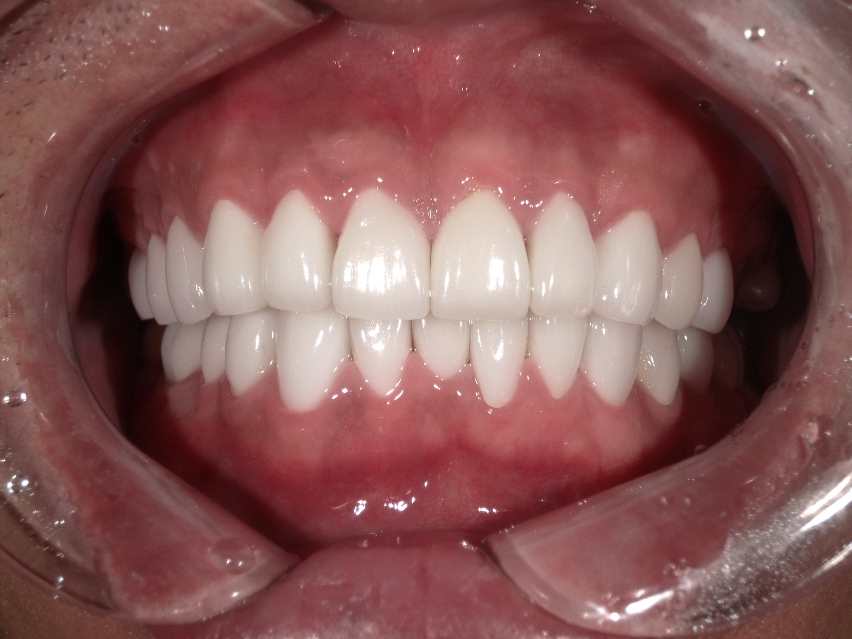

セラミック矯正症例集(ビフォーアフター)

より多くの症例をこちらのページでご紹介しておりますので、合わせてご覧ください

Case034

広島からの患者様です。

前歯を綺麗にしたい。インプラントをしたい。

という主訴で東京の歯医者をいろいろ調べて当院を選んでくださいました。

毎回、遠い中しっかり通ってくださり、選んで頂けた嬉しさと、その気持ちに応えたいという想いで診療させて頂きました。

前歯はご希望のお色でラミネートベニアでは出せない透明感のあるセラミックに上下左側7はインプラントをさせて頂きました。

左上は破折で温存不可。

骨も少なかったので、サイナスリフトも行い計五回の来院で被せ物を入れさせて頂きました。

左下は前回のクリニックでの埋入位置が深すぎて食べカスも毎回詰まる、セルフメンテナンスではら汚れも取れない。インプラント周囲炎にもなっていたので、一度前のインプラントを除去し、そこから新しくインプラントを埋入し、診療させて頂きました。

インプラント、歯並び、審美歯科にご興味のある方はいつでも相談にお越しください。

担当 理事長 佐藤 悠野